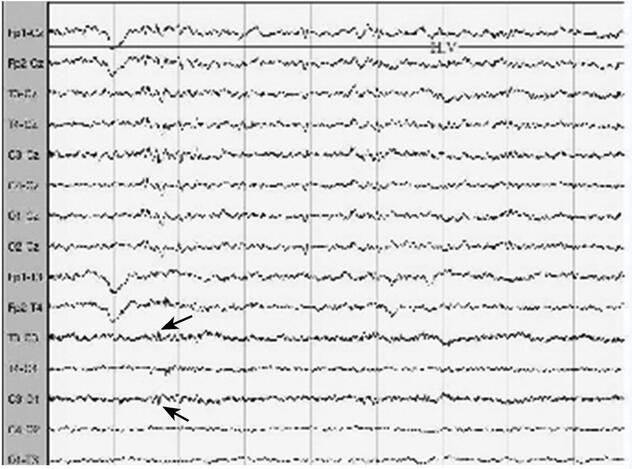

1小时条评论1 病例简介 患者男,79岁,急诊以右侧肢体轻度活动不利伴发作性双目无神19日于2009年2月12日入院。 现病史:2009年1月25日晚轻微活动中突发意识丧失、面色苍白,当时无肢体抽搐、两便失禁、两眼上翻,约10分钟自行清醒,立即来我院急诊,行颅脑CT检查为多发性腔隙性...